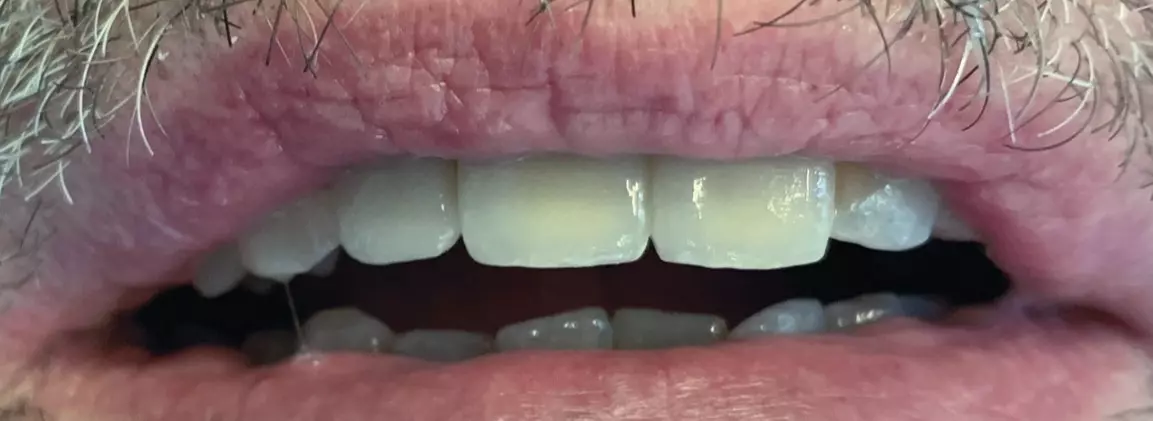

Im Frontbereich ist der Vorteil dieser Fixationsmethode darin zu sehen, dass keinerlei Schraubenzugänge zu verschließen sind, was der Ästhetik und der sensiblen Taktilität der Zunge zugutekommt (Abb. 9a-d).